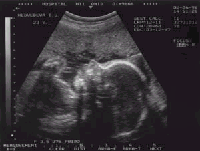

На сроке 5-6 недель уже виден эмбрион. Сердцебиение выявляют у эмбриона длиной 4-5 мм. Головку различают на сроке 7-8, а конечности - 9 недель. При такой высокой информативности УЗИ, можно выявить многие пороки развития плода во время первого триместра беременности, чтобы возможно было ее прервать путем медицинского аборта, если в этом есть необходимость.

Диагностировать пол плода на УЗИ возможно на сроке 13-16 недель. Наиболее точно срок беременности устанавливают в течение 1-го триместра, при возможности измерить копчико-теменной размер эмбриона (т.е. его длину), погрешность не превысит 3-х дней. На большем сроке погрешность может возрасти. Поэтому все беременные должны первый раз проходить УЗИ на ранних сроках (до 12 недель). На этом сроке можно выявить такое осложнение, как неразвивающаяся беременность. При этом можно различить пустое плодное яйцо (анэмбрионию) с отсутствием сердцебиения у эмбриона.